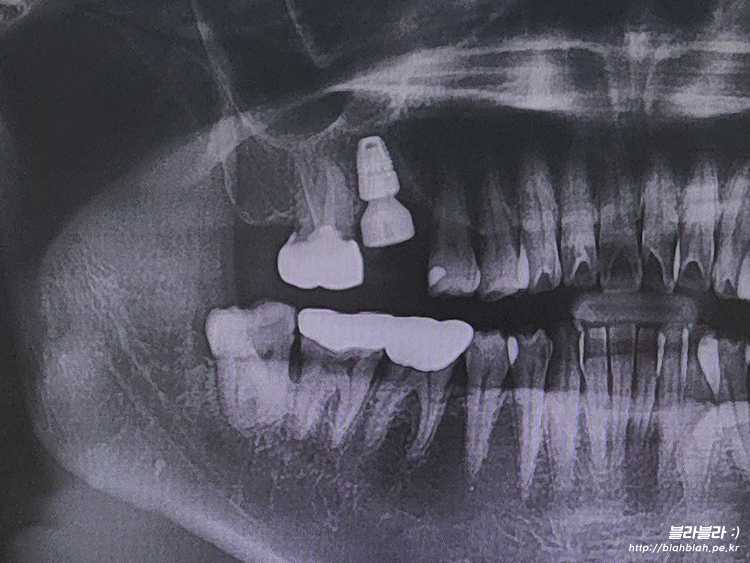

2024.03.06 내 인생에 임플란트라니...

30대에 임플란트 시작 ㅠ_ㅜ

치아관리 제대로 못한 결말은

결국 30대에 임플란트...

이걸 또 언제 마무리하고

반대편치아를 또 시작해야하는건지... ㅠ_ㅜ